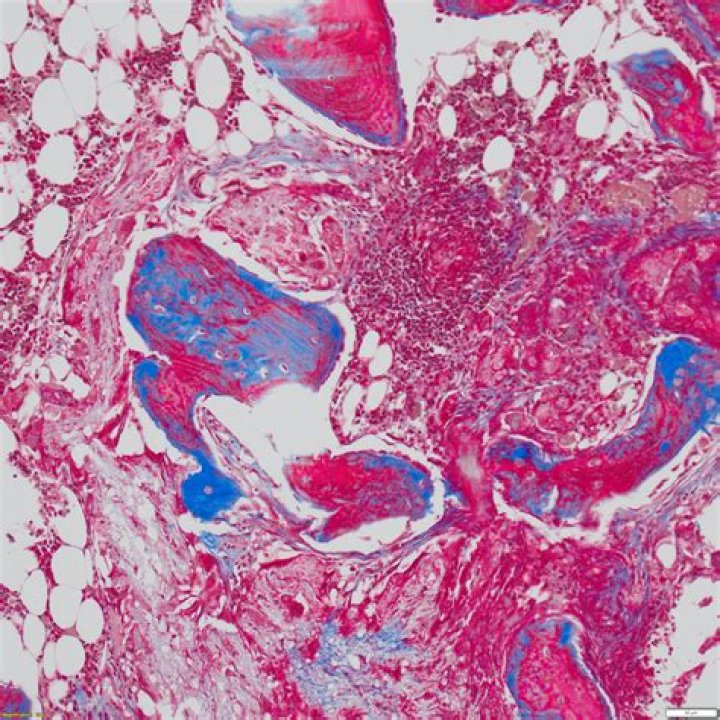

Nuclei and other basophilic (basic-liking) structures are stained blue, cytoplasm, muscle, erythrocytes and keratin are stained bright-red. Collagen is stained green or blue, depending on which variant of the technique is used.

Mason's Trichrome stain is used to highlight connective tissue fibers in a tissue section. Collagen fibers are stained a blue hue, nuclei a blue-black, and cytoplasm, keratin, and muscle fibers a range of pink to red hues.

Masson's trichrome stain is among the most common special stains applied to liver specimens. The stain imparts a blue color to collagen against a red background of hepatocytes and other structures.